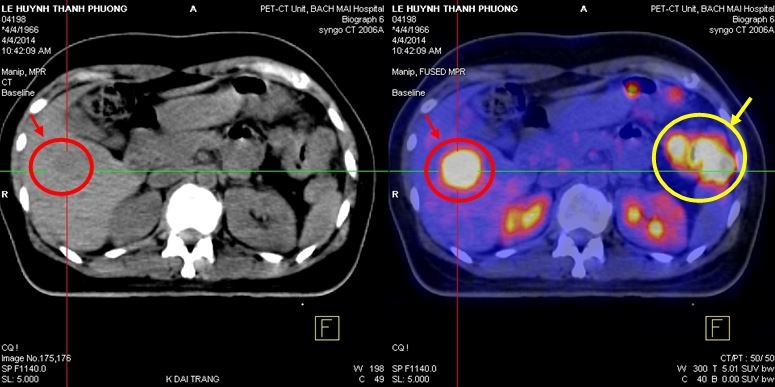

Chụp PET/CT :

- Trong nhu mô gan có nhiều khối tăng hấp thu F-18 FDG, khối lớn nhất hạ phân thùy VII, max SUV=9,1 (kích thước 3,3x4,7x3,6cm), các khối khác, max SUV=4,59 (kích thước 2,7x3,5x3,0cm), max SUV=3,2 (kích thước 2,6x2,9x2,8cm)

- Đại tràng góc lách có khối kích thước 5,2x6,8x6,7cm, làm hẹp lòng đại tràng, tăng hấp thu F-18 FDG, max SUV=12,1

Hình 1,2,3: Hình ảnh chụp PET/CT toàn thân: Vòng tròn đỏ là tổn thương tăng hấp thu F-18 FDG tại u gan và vòng tròn vàng là hình ảnh khối u đại tràng góc lách